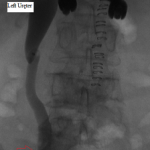

The above images belong to a middle-aged woman with cervical cancer, who developed impaired renal function when the cancer invaded and obstructed her distal ureters. Efforts by urologists to stent her ureters from below through her urethra failed, because the ureteral orifices were invisible. She was referred to the interventional radiology service for ante-grade intervention through the kidneys. Because she was prone on the table for the procedure, there is seeming reversal of her right and left sides.

Access was gained from the back into a dilated posterior calyx of each kidney and secured with a sheath. Antegrade pyelogram on each side revealed marked ureteral and calyceal dilation due to complete obstruction of the distal ureter. A wire was advanced into the urinary bladder past the obstruction, which was dilated with a non-compliant balloon when it resisted the deployment of a nephroureteral stent. The stent was successfully deployed after the balloon dilation.